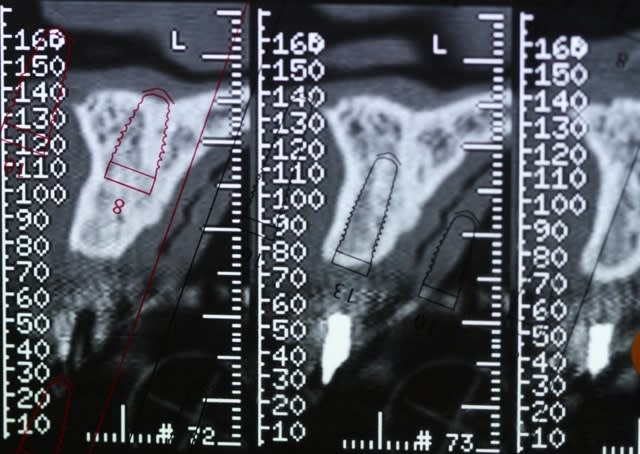

Bon voila le scann de 11-12 (pas 21-22 comme noté)

C'est vrai que j'ai à mort d'os en épaisseur.

Le manque est surtout en hauteur.

Dans tous les cas je refais 21 en même temps.

le montage guide RX laisse supposer un manque d'un mm en 12 et ok en 11. Surcomble en cj pour en éliminer au cas où avant les empreintes